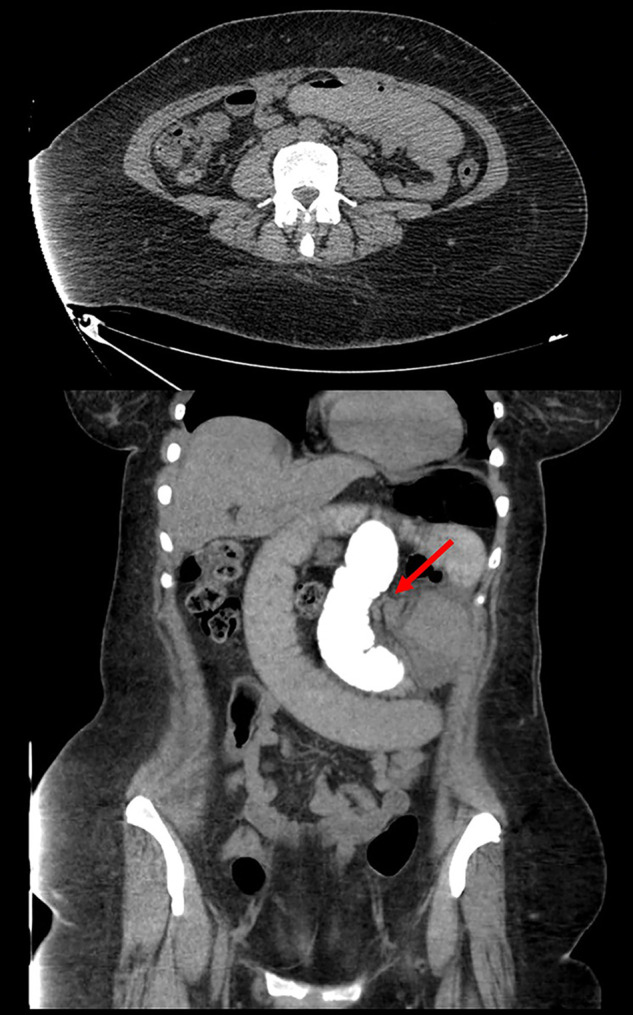

Case description: We describe the case of a 52-year-old female with a history of LRYGBP who presented with abdominal pain and emesis due to an internal hernia at Peterson's defect, requiring subsequent laparoscopic repair. On postoperative day three, the patient presented again with recurrent abdominal pain and emesis. Repeat exploratory laparoscopy found a separate internal hernia involving the jejunojejunal window with the previously repaired Petersen's defect intact.

Discussion: This case illustrates a unique scenario of a patient post-LRYGBP with multiple internal hernias at the Peterson's space and the less common jejunojejunal window, which was missed during the index surgery. Failure to identify simultaneous hernias may result in additional invasive intervention and further morbidity.